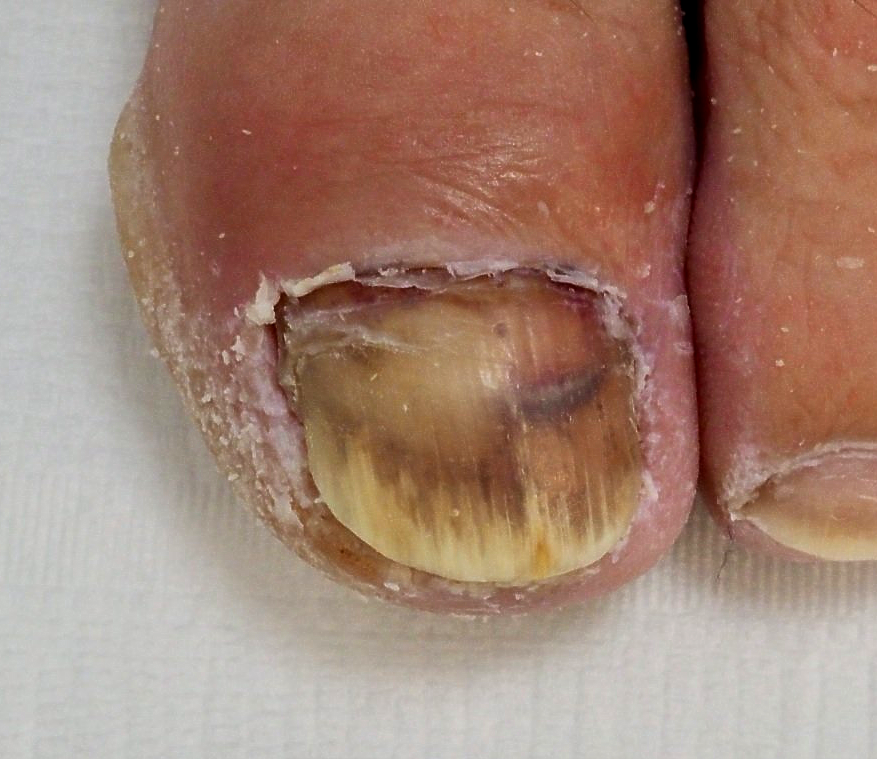

1.) Akutfall am Nagel

👉 Im Folgenden ein Akutfall der besonderen Art:

Kommt nicht sehr oft aber doch immer wieder einmal vor.

🔴 Der Nagelspan kommt bereits DURCH das Weichgewebe.

In Vergrößerung am Monitor auf Bild 2